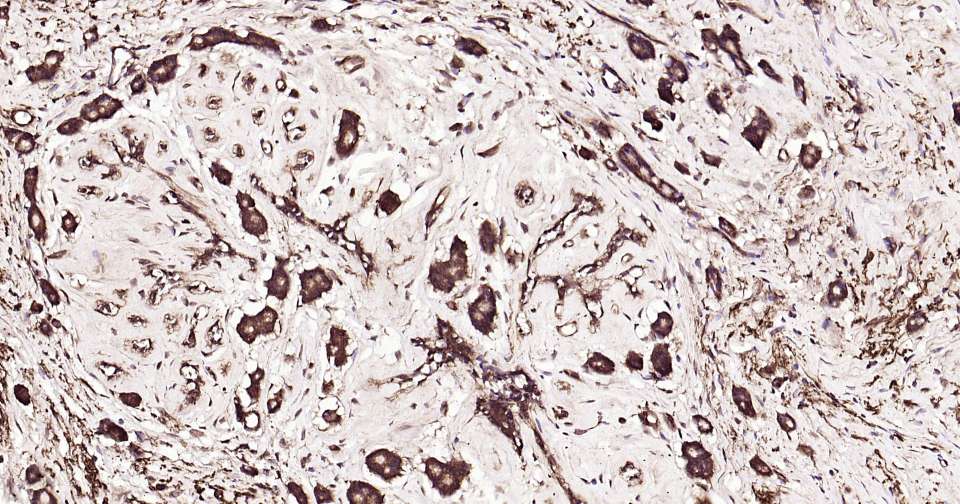

Immunohistochemical analysis of paraffin embedded human breast cancer tissue slide using IHC0348H (Human K63-linkage specific ubiquitin Kit).